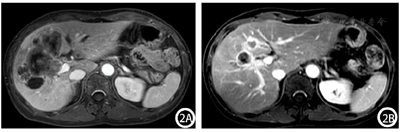

腹部增强CT:肝脏大小、形态正常,肝左内叶及肝右叶见大片状稍低密度影,增强扫描呈边缘强化,中心未见明显强化,邻近胆管扩张,门静脉右支受累,肝门区见多发肿大淋巴结,增强后强化不均匀;胆囊不大,囊内未见异常密度及异常强化灶。考虑胆管细胞癌可能,并肝门淋巴结转移(图1A)。腹部增强MRI:肝左内叶及肝右叶胆管扩张呈囊状异常信号灶,管壁增厚,其内及周围肝实质见多发片状T1WI低/稍低信号,T2WI高/稍高信号,DWI边缘呈明显高信号,中央稍高信号,增强扫描胆管及肝实质病灶呈环形强化,中央囊液不强化;胆囊底壁近肝实质处不规则增厚,DWI呈局部高信号,增强扫描轻度强化;门静脉右支受累,肝门区见多发肿大淋巴结,较大者大小约为2.0 cm×1.0 cm,形态不规则,增强后强化不均匀;胰头区见片状异常信号灶,DWI明显高信号,胰管未见明显扩张。考虑肝左内叶及肝右叶占位,胆管细胞癌可能,并肝内扩散、肝门淋巴结转移,胆囊底、胰头区、门静脉右支受侵可能(图2A)。

结合患者肿瘤分期,分别于2022年1月5日、2022年2月14日、2022年3月16日进行了3个周期的转化治疗,方案为吉西他滨+替吉奥+仑伐替尼+卡瑞利珠单抗:吉西他滨1.4 g静脉滴注、替吉奥50 mg每日2次(服用4周停2周)、仑伐替尼8 mg口服每日1次、卡瑞利珠单抗200 mg。患者规律经以上治疗后,于2022年4月11日返院,行腹部增强CT:对比前片:肝脏占位病变范围较前稍缩小、强化程度大致同前,肝门区肿大淋巴结本次扫描未见显示(图1B)。腹部增强MRI:对比前片,肝左内叶及肝右叶占位较前明显缩小,肝门部肿大淋巴结未见显示,胆囊底部结节状异常信号灶范围较前缩小,胰头区受累病变DWI未见高信号,门静脉右支及右侧肝内胆管受累同前(图2B)。结合影像学检查,患者ICC分期:T2N0M0(Ⅱ期),转化治疗成功,达到降期目标,遂完善术前准备后,于2022年4月20日在全身麻醉下行"右半肝切除+胆囊切除+腹腔淋巴结清扫(第8组3枚、第12组3枚、第14组4枚)+胆肠吻合+腹腔冲洗置管引流",手术顺利,术后恢复良好。术后自2022年6月9日开始,患者定期每3周返院接受全身化疗及免疫、靶向治疗,方案:吉西他滨1.4 g每3周1次+培他滨1.75 g每日2次(治疗2周停药1周)+仑伐替尼8 mg口服每日1次+卡瑞利珠单抗200 mg每3周1次;经3个周期治疗后,患者CA19-9无明显下降,遂改换方案:吉西他滨1.4 g每3周1次+卡培他滨1.75 g每日2次(治疗2周停药1周)+顺铂40 mg每日1次(连用3 d)每3周1次,以此方案治疗至今。